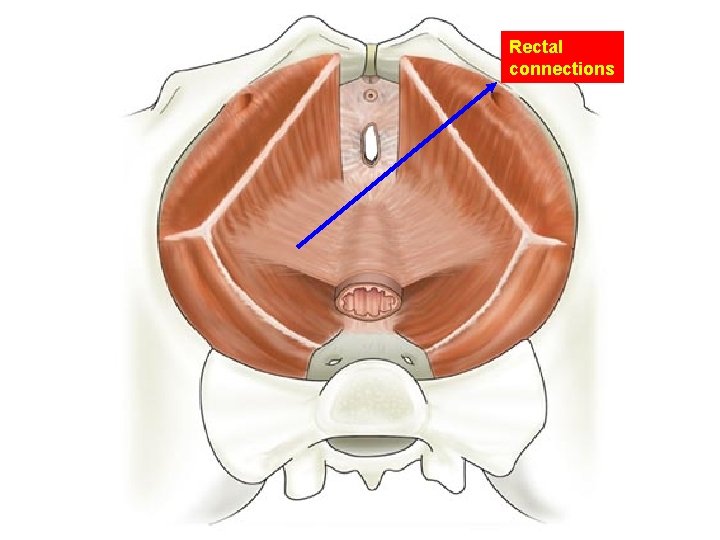

Rectal connections